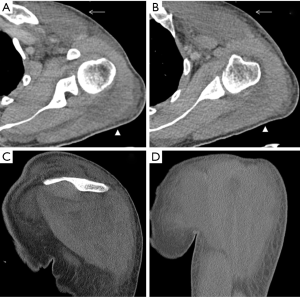

The pectoralis major is the most superficial of the anterior scapular muscles. It originates on the clavicle, sternum, rectus sheath, and on the costal cartilages of the first six ribs, inserting on the lateral lip on the bicipital groove. The frequency of injuries of the pectoralis major muscle has been increasing during the past two decades (30). This trend can be attributed in part to increasing cases of sports-related trauma and the growing popularity of weight-training regimens such as bench press weight-lifting exercises. Patients are generally young and active. The most common mechanism of injury is excessive tension on a maximally contracted muscle (31). Injuries of the pectoralis major can be categorized according to their location: muscle origin or belly, musculotendinous junction, intratendinous region, humeral insertion, or area of bone avulsion at the humeral attachment. Most of pectoralis major injuries occur at the humeral insertion (59%) and musculotendinous junction (24%) (32). Patients with injuries at the muscle origin or belly, including contusions and strains, usually are treated conservatively. Injuries involving bone avulsion at the humeral attachment may benefit from a primary fracture fixation (33).

A normal pectoralis major tendon should have uniform low signal intensity on MR imaging. Like US (34), tears of the pectoralis major tendon seen on MR imaging exhibit different degrees of tendon abnormality, depending on the degree of injury. A grade I strain of the muscle belly will have feathery intramuscular fluid-sensitive signal intensity, which represents oedema and/or haemorrhage. Grade II injury will appear as a partial tear with an intramuscular hematoma, while grade III injury has a complete tear with possible retraction (Figures 11-13). As a matter of fact, a partial tear involving only the posterior sternal segments, the anterior clavicular head and tendon will be intact, with the long head of the biceps tendon in place. With complete tears involving both the sternal head and the clavicular head, however, there will be disruption of the entire tendon, with anterior displacement of the long head of the biceps tendon (35).